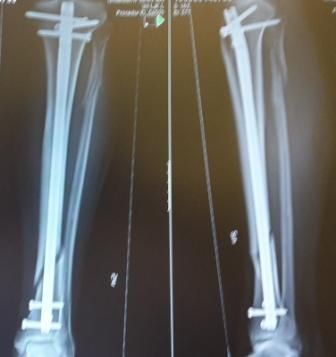

Dr hab. n. med. Ireneusz Babiak - ponad 30-letnie doświadczenie zawodowe zdobywane w trakcie pracy i szkoleń w szpitalach klinicznych w Polsce, Niemczech, Szwajcarii i Szwecji. Specjalizuje się w diagnostyce i leczeniu chorób stawów kolanowych, biodrowych, barkowych, kręgosłupa, deformacji stopy, terapii podciśnieniowej ran (tj NPWT) systemami VAC, Pico, Avelle. Wykonuje operacje: endoprotezy stawu biodrowego i kolanowego ( w ostatnim roku 200 endoprotez implantowanych osobiście i asysta do kolejnych 200 endoprotez), zespół cieśni nadgarstka, palec zatrzaskujący, paluchy koślawe (haluxy), palce młotkowate, zespolenia złamań kości, zaburzenia zrostu, operacje rewizyjne endoprotez stawów, operacyjne leczenie zapaleń kości stawów z zastosowaniem biomateriałów, przeszczepy skóry. Do roku 2017 adiunkt oraz ordynator Oddziału IV w Klinice Ortopedii Traumatologii Warszawskiego Uniwersytetu Medycznego (WUM), oraz wykładowca na English Division Medical University of Warsaw. W roku 2018 stanowisko överläkare - specjalista odpowiedzialny za endoprotezoplastykę biodra i kolana w Klinice Ortopedii w Eskilstunie w Szwecji. Wykładowca na kursach szkoleniowych z operacji rewizyjnych endoprotez stawów, zapaleń kości i stawów, planowania w endoprotezoplastyce stawów, powikłań w ortopedii. Członek towarzystw naukowych: PTOiTr (Polskie Towarzystwo Ortopedyczne i Traumatologiczne), EBJIS (European Bone and Joint Infection Society), PTZS (Polskie Towarzystwo Zakażeń Szpitalnych).

Zdjęcia i filmy